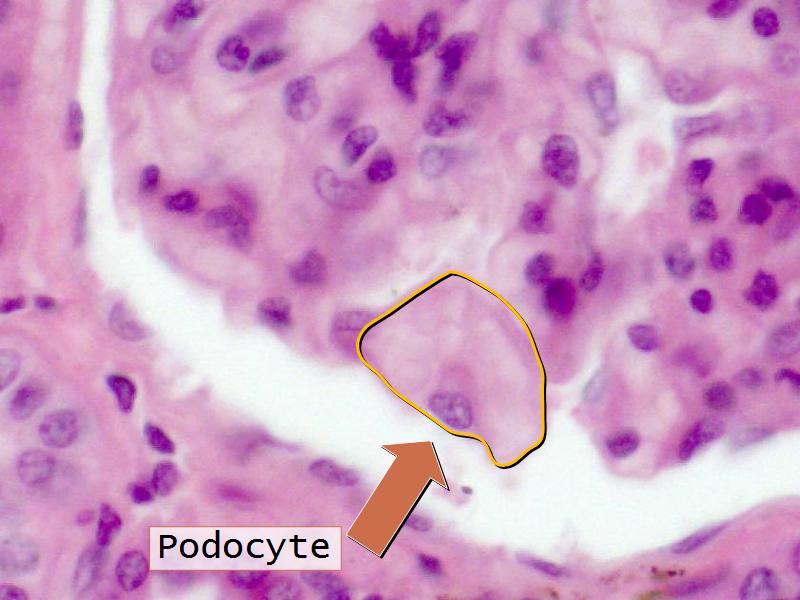

- Kidney = cuboidal, squamous

- Structure of the nephron and collecting tubules

- The renal corpuscle